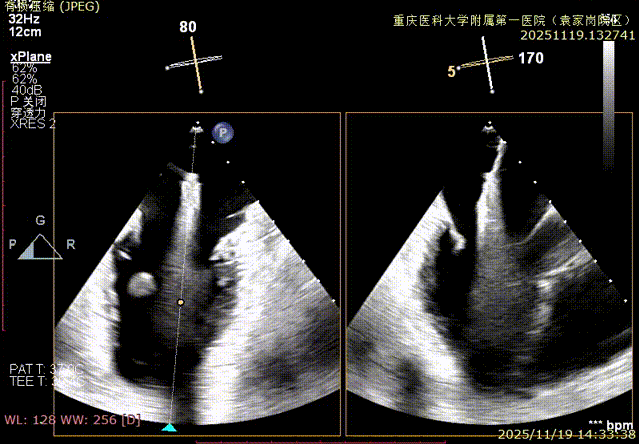

术前食道超声评估:三尖瓣重度反流,FTR6+,反流位于前隔、中央,后隔。瓣叶粘液样变性,后隔可见4.6mm gap。

视频1:术前Bicom